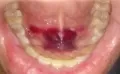

У меня во рту на нижней челюсти под языком примерно раз в 3 дня вырастает пузырь (размером примерно с зерно граната и цвета такого же), лопается и из него вытекает немного крови. Болевых ощущений нет. Такое у меня впервые, аллергии не было. Это длится примерно 3 недели.

Подскажите, пожалуйста, что это может быть и куда мне обратиться?